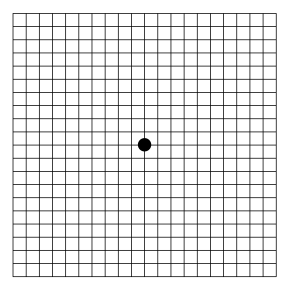

| Amsler grid | |

Amsler grid, as seen by a person with normal vision | |

| Purpose | Used to detect vision problems resulting from damage to the macula or the optic nerve[1] |

| Test of | Central visual field |

In the test, the person looks with each eye separately at the small dot in the center of the grid. Patients with macular disease may see wavy lines or some lines may be missing.

Chart 1 is the basic version, which is the most familiar and widely used chart among all the charts. In this chart the grid consists of 0.5 cm squares (each for 1° visual field), which totally measures 10 cm X 10 cm size. Most commonly grid is in white color with black background.[3] Grid with black lines in white background is also available (see infobox picture).